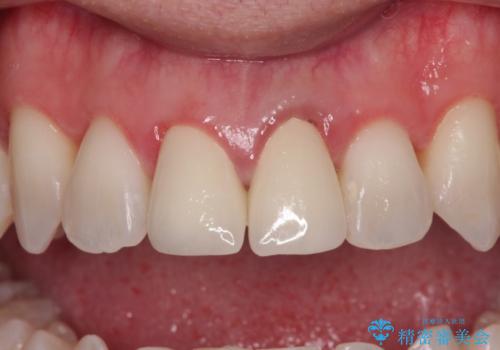

- 他院でインビザラインによる矯正治療を行っているものの、前歯の変色が気になるとのことで来院された患者様です。

インビザラインでの矯正治療がそろそろ終了とのことで、新しいインビザラインセットを発注する前に気になっている前歯2本をオールセラミッククラウンにて補綴治療を行うこととしました。

歯肉の腫脹は大分改善されましたが、なかなかご自身でのブラッシングが上達せず、やや腫脹残った状態での治療終了となりました。